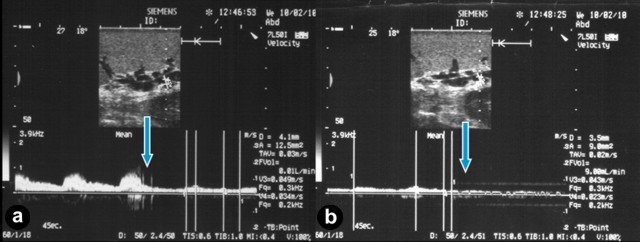

According to the changes in US findings after the above-mentioned successive clampings of the arteries supplying the spleen and stomach, the patients were divided into two groups. In Group 1 (20 cases, 87.0%), there was a direct anastomosis between the left and right gastroepiploic arteries and, in Group 2 (3 cases, 13.0%), the gastroepiploic arcade was disconnected. In Group 1, the splenic artery clamping was followed by a 1- to 3-fold fall in blood flow volume brought about by the drop in mean systolic velocity, but the spectrum of the Doppler shift corresponded to the arterial wave with a large diastolic component (Figure 4a). In all cases except one (#8, Table 3), upon the splenic artery being clamped, left gastroepiploic artery clamping, even of a collateral type, caused the arterial blood flow to cease (Figure 4b). Upon the splenic artery being clamped, clamping of the short gastric arteries before or after the left gastroepiploic artery cross-clamping did not alter the qualitative or quantitative parameters of the flow. In the case of the sole exception (#8), after the clamping of the splenic artery and the left gastroepiploic artery, hilar collateral flow was detectable but it was decreased fourfold and was accompanied by marmoreal staining of the spleen (Table 3).

Figure 4. Intraoperative color Doppler ultrasound of the splenic hilum at distal pancreatectomy in cases of a direct anastomosis between the left and right gastroepiploic arteries. a. A 3-fold fall in blood flow volume after splenic artery cross-clamping (arrow). b. Upon the splenic artery being clamped the left gastroepiploic artery clamping (arrow) caused the arterial blood flow to cease. Upon the splenic artery being clamped, the clamping of the short gastric arteries before or after left gastroepiploic artery cross-clamping did not alter the flow parameters. |